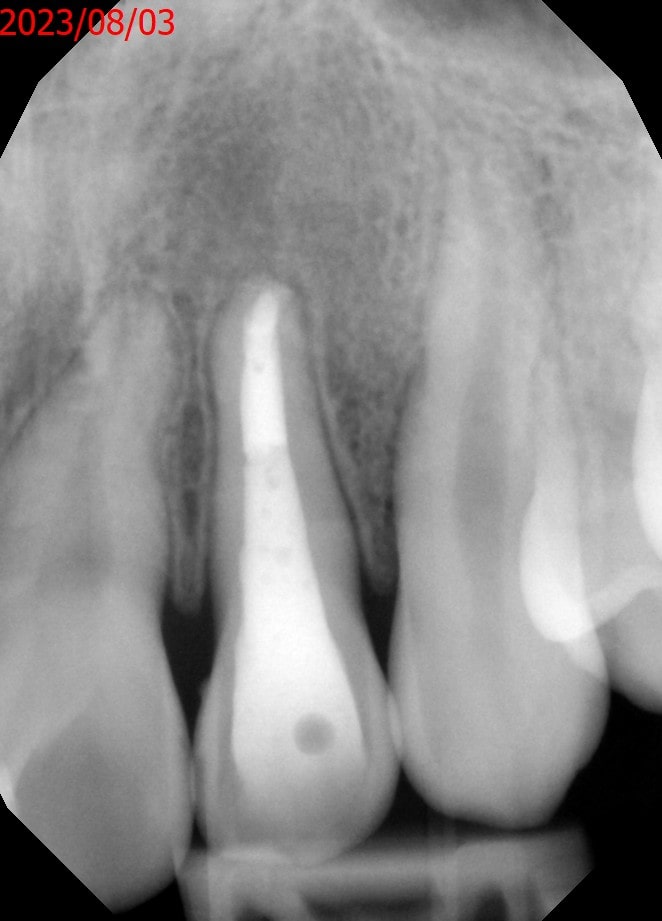

症例4 非外科 病変あり 前歯

治療前

症例4 非外科 病変あり 前歯 治療前

石灰化にて治療困難の為、紹介にて来院